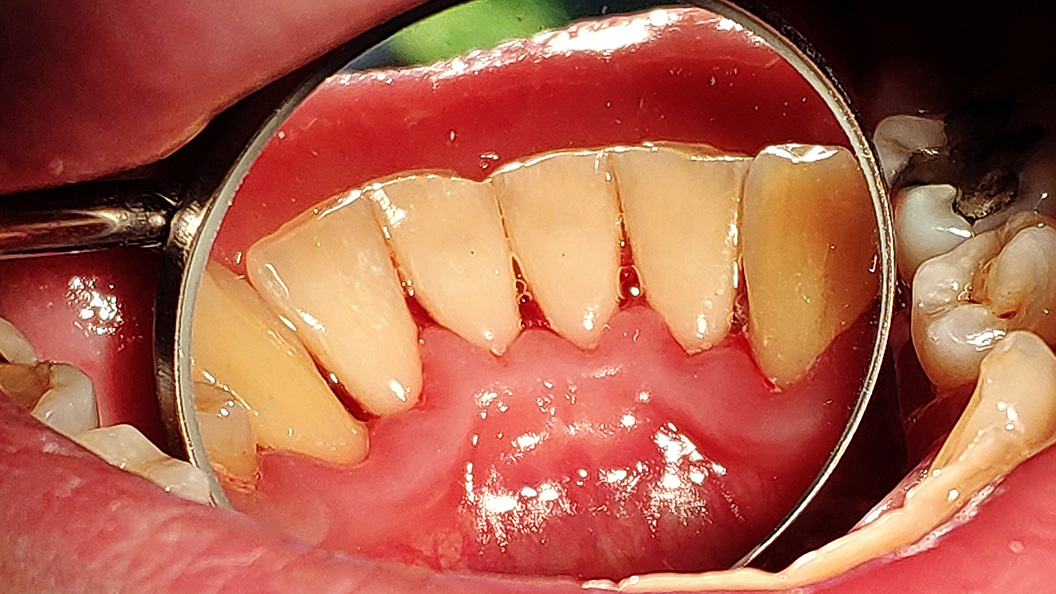

До и после лечения

В ходе процедуры Антоном Алексеевичем были проведены следующие работы:

- удаление над- и поддесневых зубных отложений с помощью ультразвукового аппарата;

- чистка зубов аппаратом Airflow;

- полировка зубов щеткой с пастой "Detartrine Z";

- медикаментозная обработка десны 3% перекисью водорода и 0,05% хлоргексидином;

- даны рекомендации по ежедневной личной гигиене полости рта.